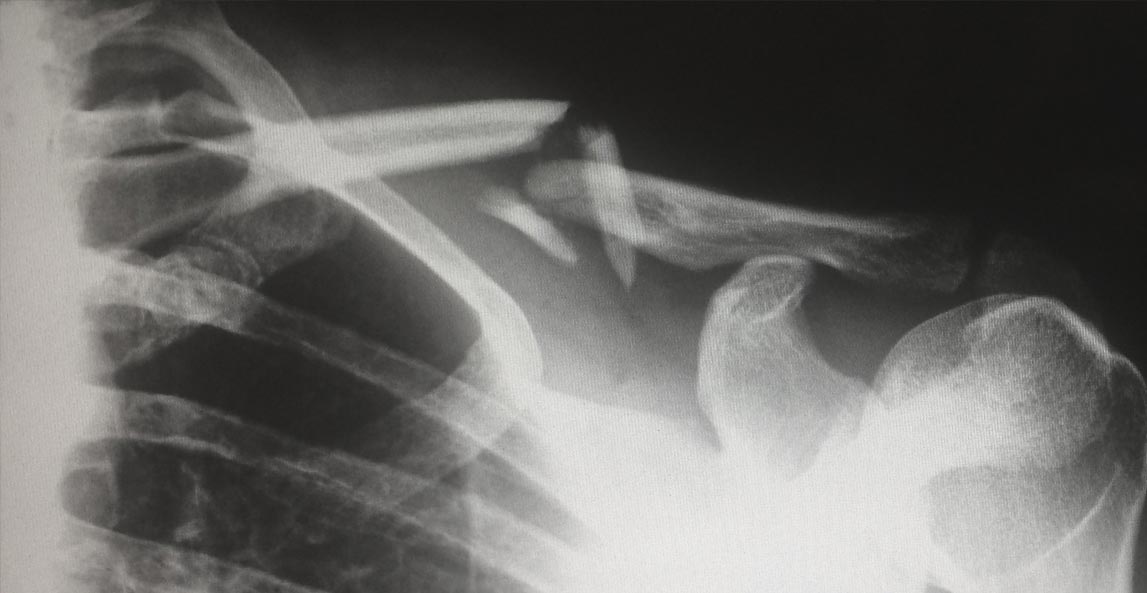

Every patient should received proper treatment for medical conditions. Errors by healthcare providers can include medication errors, surgical errors, birth injuries, or misdiagnoses of conditions. The firm’s partners began their careers representing hospitals and other healthcare providers. With malpractice cases, we now exclusively represent injured patients and families of patients killed by medical errors.